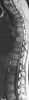

Congenital thoracolumbar vertebral wedging

Congenital vertebral anomalies are a collection of malformations of the spine. Most, around 85%, are not clinically significant, but they can cause compression of the spinal cord by deforming the vertebral canal or causing instability. [Source: Wikipedia ]